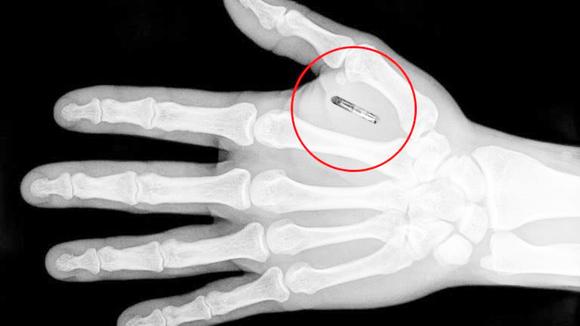

这种植入芯片的外形是圆柱体,长12毫米、直径2毫米。它会被植入用户的户口。没错,需要用一个直径2毫米加的巨型针筒。那场面还是有些可怕的。理论上来说,正常生活中感受不到它的存在。这种芯片的主要用途,就是可以用来替换生活中的各种门卡、地铁卡及车票等。

植入芯片的主体是一颗NFC装置。这种芯片可以通过无线电讯号与周围别的机器交流,从而进行开锁、验证身份等行为。

这种植入芯片并不需要电池,可以通过附近识别NFC信号的机器供电,所以不用担心十天半个月后就需要把它取出来换电池。据了解,目前瑞典已有超过3000人植入了这种芯片。